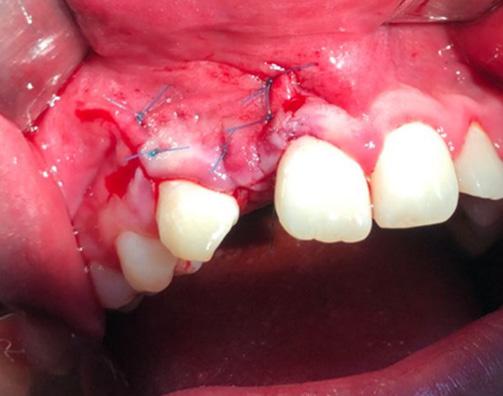

Durante el estudio, la cabeza de cada estudiante fue posicionada en relación al plano de Frankfurt (paralelo al piso), mismo que se logró con una regla nivel de 30 cm; dicho plano anatómico se extiende desde el agujero infraorbitario a la parte media del borde superior del conducto auditivo externo (12), estos reparos anatómicos se identificaron en el estudiante mediante la palpación digital del borde inferior de la órbita y a simple vista del trago del pabellón auricular (figura 1).

Quelca-Portugal-Yujra-Chuquimia

Seguidamente y mediante palpación se localizó de forma bilateral el ángulo mandibular, el reborde orbitario lateral y la arteria facial de cada estudiante, ésta última estructura se identificó a nivel del borde inferior del maxilar inferior, percibiendo sus pulsaciones con facilidad. Con un lápiz dermográfico se marcó un punto en la piel donde se localizó a estas tres estructuras. Desde el punto marcado que representaba a la arteria facial, se trazó una línea vertical y ascendente hasta la referencia anatómica más relevante, identificable y no modificable por procesos infecciosos submandibulares (arco cigomático). Finalmente se determinó la distancia entre el borde lateral de la órbita y la proyección vertical ascendente de la arteria facial sobre el arco cigomático (figura 1).

Fuente: Elaboración propia, julio 2019

Figura 1. Puntos y líneas utilizadas para la localización de referencia anatómica no modificable sobre la base de la arteria facial. Localización de referencia anatómica inmodificable sobre la base de la arteria facial en infecciones submandibulares odontogénicas